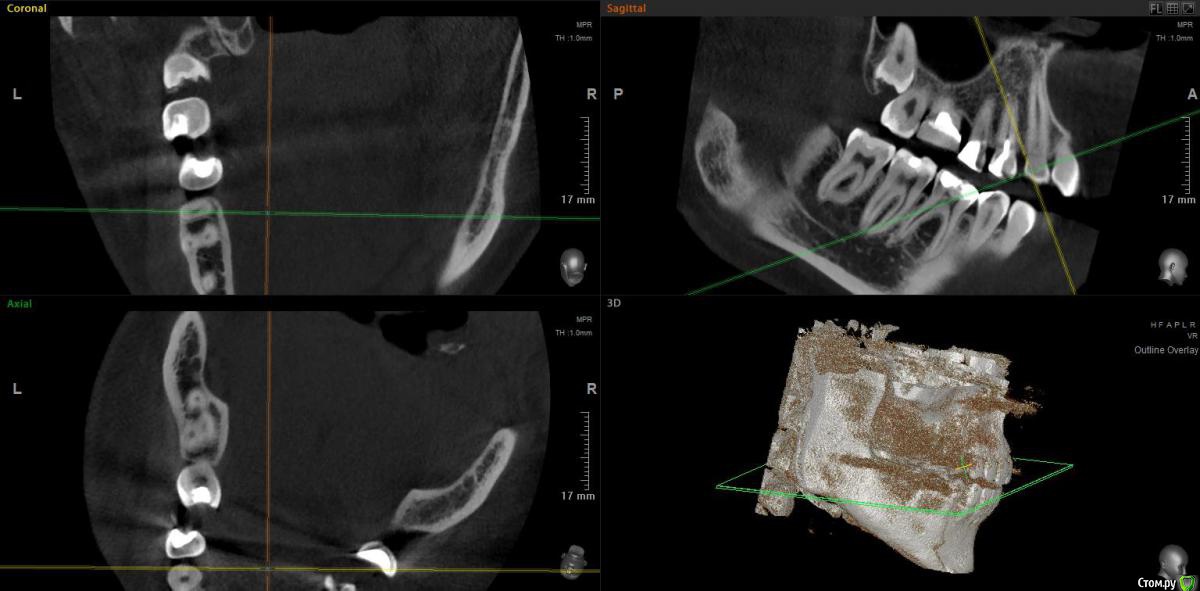

bbss Опубликовано 6 июля, 2018 Автор Поделиться Опубликовано 6 июля, 2018 Здравствуйте, я в итоге 12 на 8.5 сделала.Посмотрите пожалуйста, можно ли по этому снимку что-то сказать? Ссылка на комментарий

Irouil Опубликовано 7 июля, 2018 Поделиться Опубликовано 7 июля, 2018 Сомневаюсь, что зуб виноват в Ваших симптомах. Ссылка на комментарий

bbss Опубликовано 7 июля, 2018 Автор Поделиться Опубликовано 7 июля, 2018 Сомневаюсь, что зуб виноват в Ваших симптомах.Скажите, а нужно ли его удалять? Мне еще кажется, что он возможно давит на рядом стоящий недепульпированный зуб, поэтому и боль? ( Хоть другие симптомы и не из-за него). А он может сам проехаться со временем? Ссылка на комментарий

Irouil Опубликовано 7 июля, 2018 Поделиться Опубликовано 7 июля, 2018 Навряд. Иногда ретенированные зубы в процессе прорезывания могут "продавить" дефект в корне соседнего зуба и вызвать пульпит, но в Вашем случае создаётся впечатление, что они просто в контакте. Ссылка на комментарий

Irouil Опубликовано 7 июля, 2018 Поделиться Опубликовано 7 июля, 2018 (изменено) Вы неплохой ракурс выбрали, хотя и можно ещё покрутить для детализации. Тем не менее, мне кажется надо в первую очередь обратить внимание на пространство между 5-м и 6-м зубами, а также на сам 5-й и на 4-й зубы. Вероятнее болит что-то в этом пространстве - либо причина в парадонтите, либо в пульпите одного из этих зубов. Повторюсь, Ваши симптомы намекают на невралгию, надо бы ее исключить у невролога. Изменено 7 июля, 2018 пользователем Irouil Ссылка на комментарий

bbss Опубликовано 7 июля, 2018 Автор Поделиться Опубликовано 7 июля, 2018 (изменено) Там где 5 и 6 тоже болит, даже наверное больше там болит сейчас, я просто думала, что оно просто отдает, а на 5-ом у основания какое-то черное пятно, но врач сказала, что это не кариес, может быть шов (??), правда реакции на холодное/горячее совсем нет, в 5-ом еще ощущения, но они давно были, как будто он стянут. К неврологу с болями в районе зубов именно не обращалась, а по поводу основных симптомов они ничего не находят, поэтому решила, что может от зубов это идет.А можно еще спросить, пожалуйста, может быть Вы тоже знаете. Я когда жую, или даже когда сейчас пыталась посчитать зубы языком, то в затылке больно, может ли такое челюстная система давать? Изменено 7 июля, 2018 пользователем bbss Ссылка на комментарий